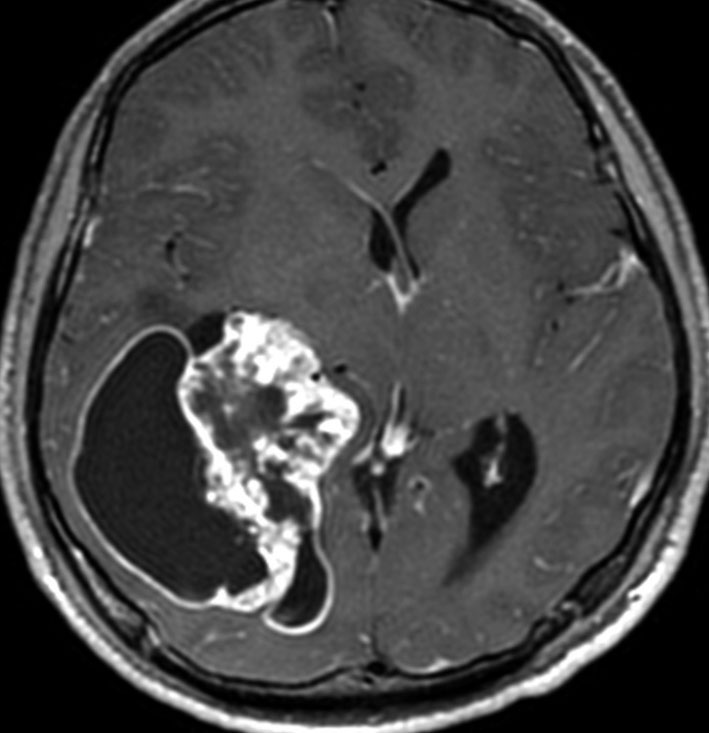

第4脳室床に発生した典型的な上衣腫 EPN-PFA の画像です。水頭症になって,頭痛と嘔吐,意識障害で発症しました。典型的なMRI画像と病理所見です。MRIでは第4脳室からマジャンディー孔を越えて脊髄背側まで長く腫瘍が伸びています。腫瘍内部に小さなのう胞が複数みられます。病理像では,血管周囲に細胞核がない無核野が認められます。血管周囲に伸びた繊細な単極性突起が集まった領域です。これは,血管周囲偽ロゼット perivascular pseudorosette という上衣腫に特徴的な病理所見です。

テント上 退形成性上衣腫 グレード3:EPN-ST-RELA negative

膠芽腫を思わせるような,腫瘍内部の壊死,のう胞形成,出血があります。高度の血管増生と動静脈シャントがあり,早期腫瘍静脈描出 early venous fillingがみられます。10代のおそらく右側脳室三角部辺りから発生した退形成性上衣腫です。激しい出血がありましたが全摘出 gross total removal しました。リスクをかえりみない手術も必要です。画像所見も病理組織像も超悪性腫瘍なのですが,治る可能性があるタイプです。